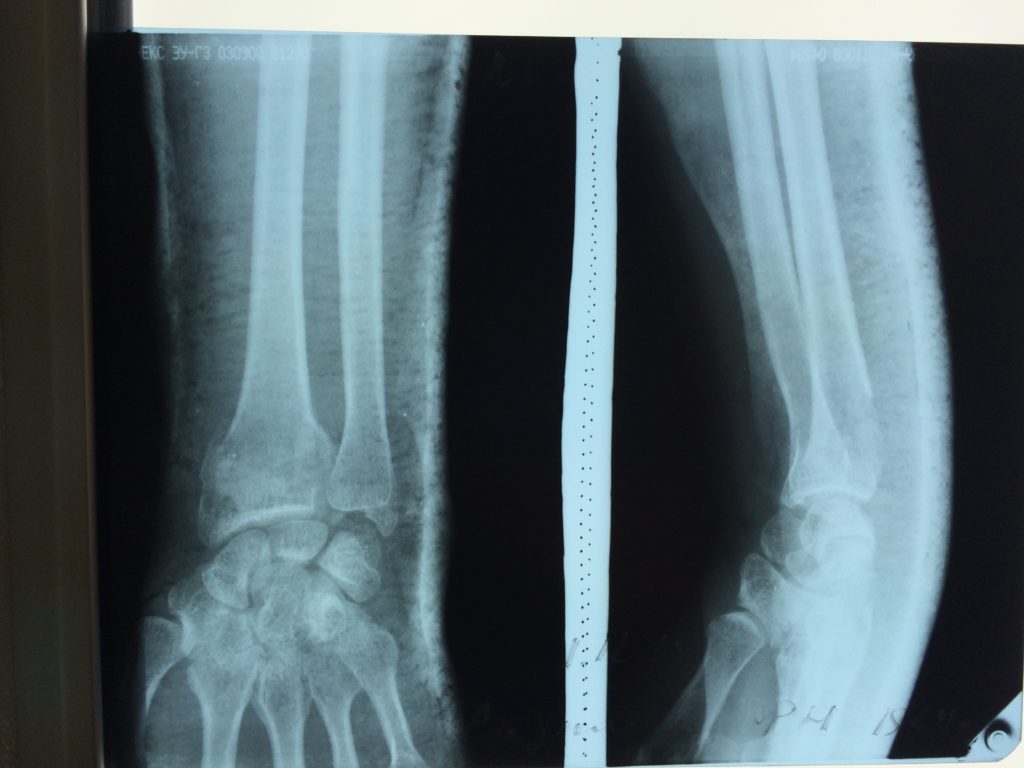

Использование материала Остеоматрикс при полифокальном внутрисуставном импрессионном переломе дистального эпиметафиза лучевой кости

Использование материала Остеоматрикс при полифокальном внутрисуставном импрессионном переломе дистального эпиметафиза лучевой кости.

Операция - открытая репозиция, остеосинтез лучевой кости пластиной с костной ксенопластикой материалом "Остеоматрикс". На контрольных снимках в три месяца имеется консолидация перелома, миграции фиксатора нет, имеется остеоинтеграция ксенопластического материала.

Отдаленные результаты через 3 (три) месяца:

Отдаленные результаты через 6 (шесть) месяцев